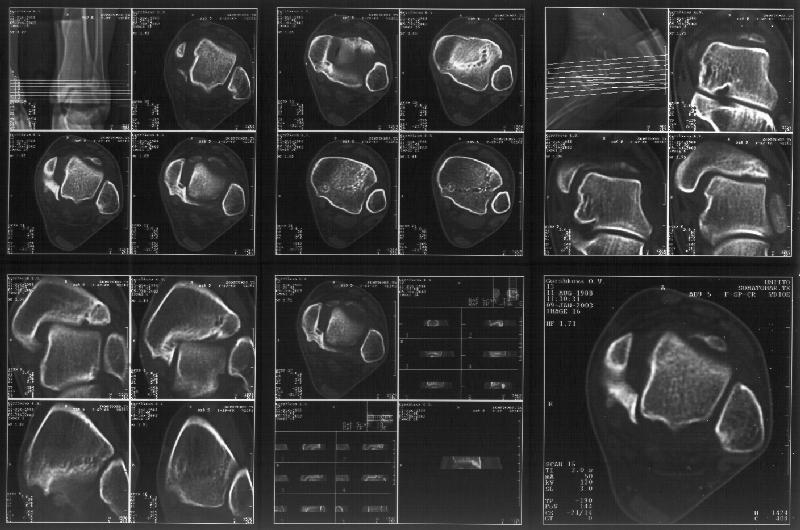

На следующий день пациентке сделали КТ. Может быть, после просмотра картинки будут другие предложения? Не убрать ли ве-таки этот фрагмент

позади внутренней лодыжки, который оттесняет таран кнаружи?

Здесь 4 среза, начиная от основания лодыжки и проксимальнее. Где, по Вашему мнению, проходит линия перелома, отделяющая переднюю часть внутренней лодыжки от большеберцовой кости? Заранее спасибо.

Сегодня пациентке сделали сравнительную КТ. А ксиальные и Фронтальные срезы приложены. Ваше мнение?

Фронтальные

Аксиальные